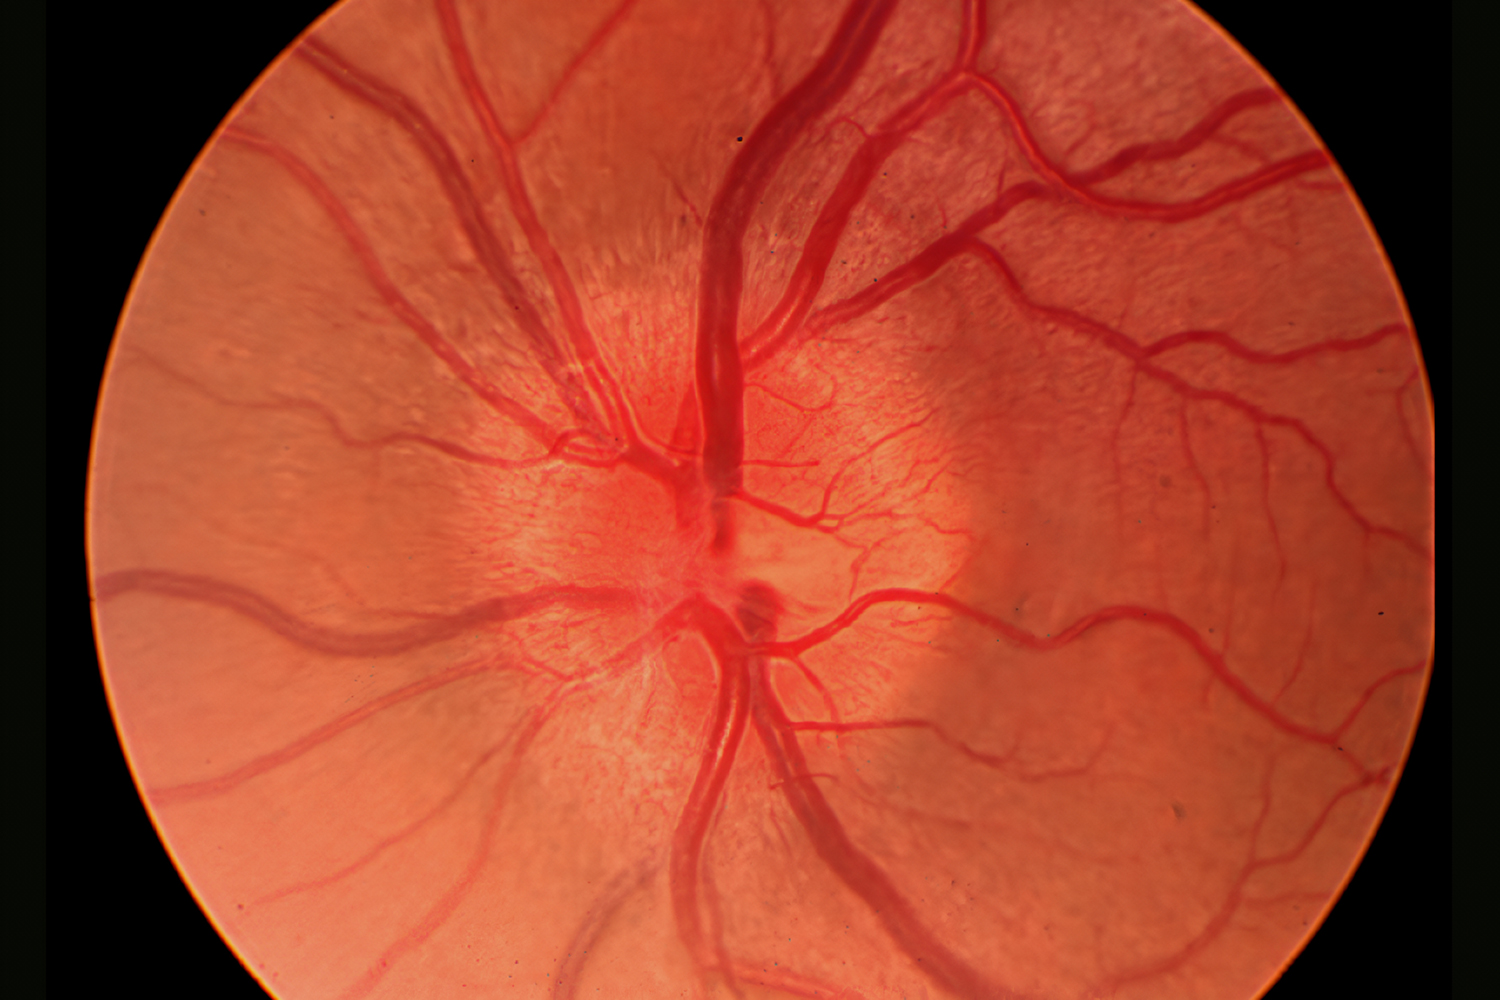

- 视网膜检查 (眼底照相):拍摄照片以观察您的眼后部,包括视网膜、视神经、黄斑和眼部血管,有助于检测青光眼、黄斑变性和糖尿病视网膜病变等疾病

视神经萎缩 (OA)

视神经萎缩 (OA) 是指视神经的退化,视神经是连接视网膜和大脑的关键通路,其退化是由各种疾病引起的视神经纤维、神经节细胞及其轴突的病理损伤所致。这种退化会导致视功能逐渐下降,其特征是不同程度的视觉功能障碍,包括视力下降、视野缺损 (通常是向心性缩小)、色觉改变,严重时甚至失明。临床上,OA 分为原发性 (下行性),即神经本身直接受累,和继发性 (上行性),即损伤由其他疾病引起,如颅内压升高、炎症或血管问题。诊断依赖于评估视力下降、视野缺损、视盘苍白或苍白以及视网膜神经纤维层缺损。在眼底检查中,早期体征包括视盘苍白、边缘清晰的视神经乳头苍白或苍白、视网膜血管变细和黄斑中心凹反射模糊。有效的西医治疗 OA 取决于识别和解决根本原因,因为逆转损伤通常很困难。